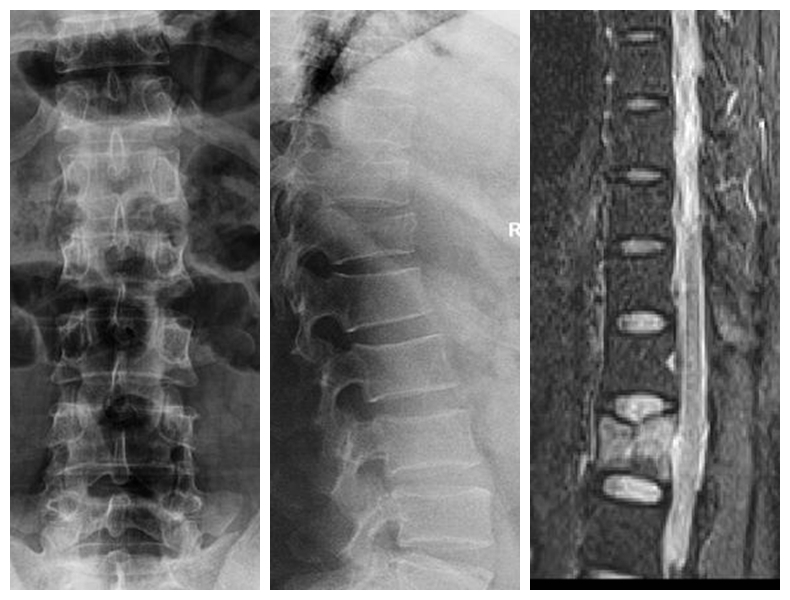

經(jīng)皮胸腰椎骨折椎弓根螺釘內(nèi)固定技術(shù)

傳統(tǒng)胸腰椎骨折切開復(fù)位椎弓根螺釘內(nèi)固定術(shù)組織創(chuàng)傷大、失血量大、住院時(shí)間長、下地時(shí)間晚、費(fèi)用高。經(jīng)皮胸腰椎骨折椎弓根螺釘內(nèi)固定技術(shù)組織創(chuàng)傷小、失血少、住院時(shí)間段、下地時(shí)間早、費(fèi)用低。

典型病例:患者**,男性,43歲,因“摔傷致胸腰背部疼痛、活動(dòng)受限2小時(shí)”門診平車入院。雙下肢肌力、感覺及肌張力正常。

本例患者術(shù)后5天在腰圍保護(hù)下獨(dú)立下床,雙下肢肌力感覺正常。